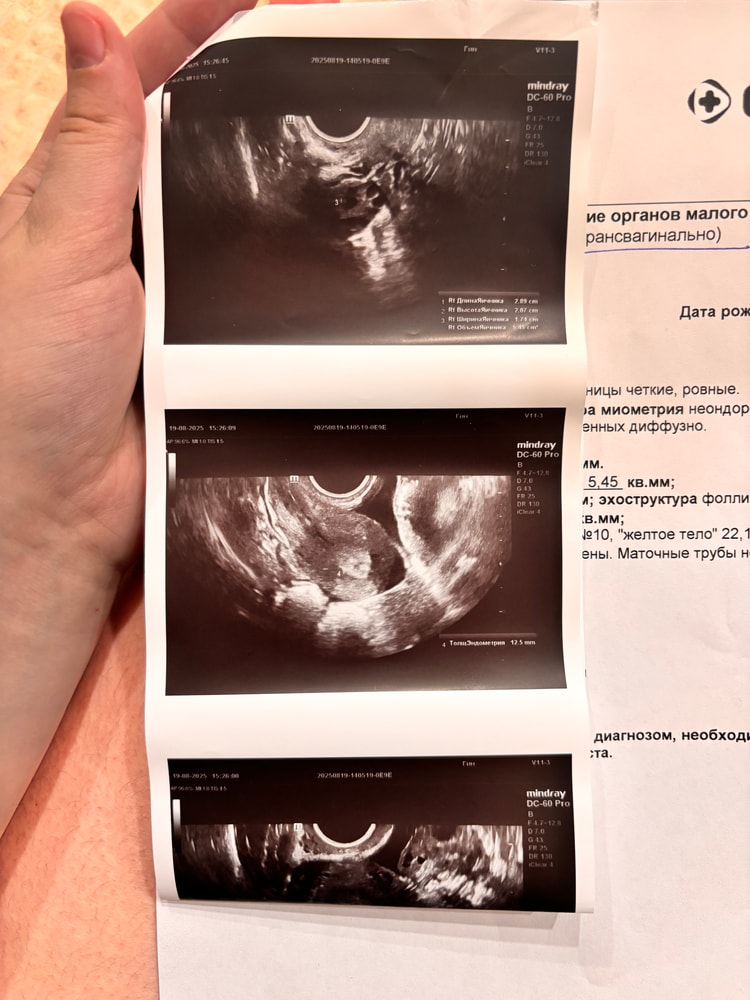

Приложу фото яичника, вчера писала пост о том, что уже даже у хирурга была из за боли, боль в яичнике при нажатии, при чихе, смехе, кашле, сегодня сходила к гинекологу, пока смотрела на кресле и параллельно давила на живот я аж заорала от боли, она сказала что боль от кисты жёлтого тела(26 мм) ..Но мне не верится, что от жт такая боль может быть..